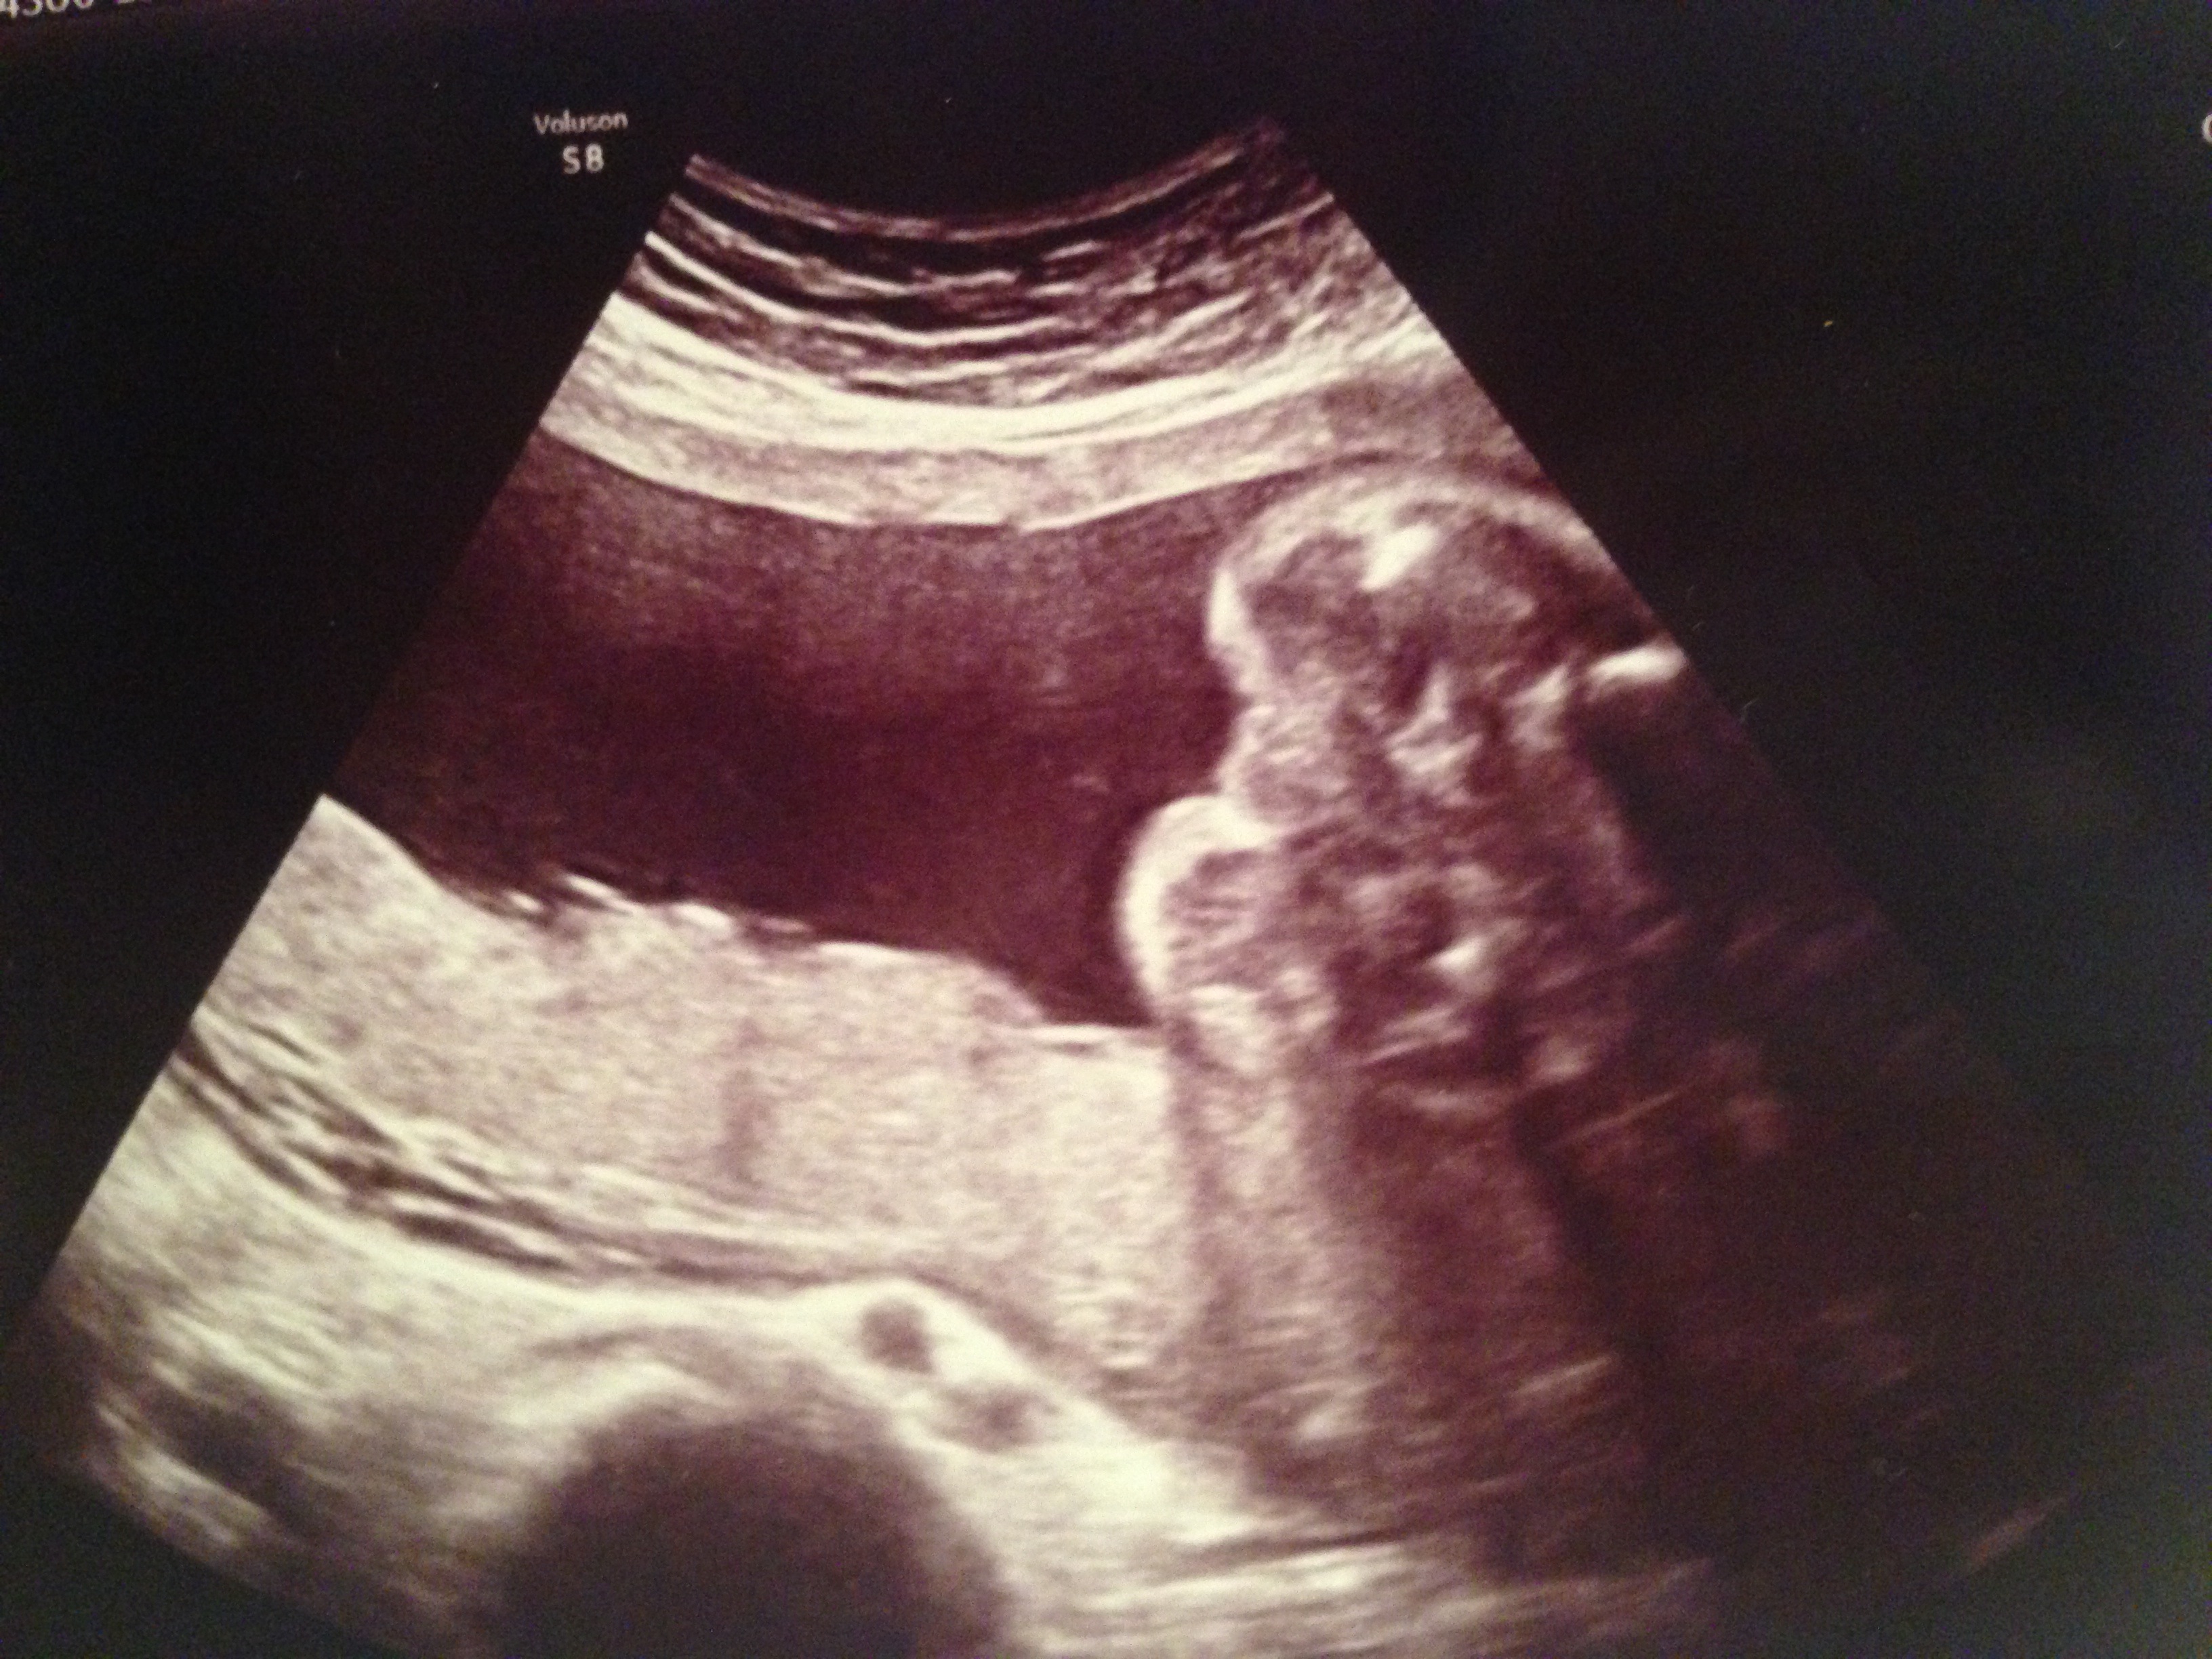

This is the 24 week ultrasound of the baby's bottom. Not sure if it is a boy or girl, but we really want to know! Any opinions would be appreciated :)

It's not the best angle for a potty shot. It appears to me that the camera is rotated too far toward the bum, you want a little more "parts" in there. It truthfully could be the bottom of a scrotum. Or the lower parts of vaginal lips. Sorry. Maybe a more experienced guessed can see some clue.